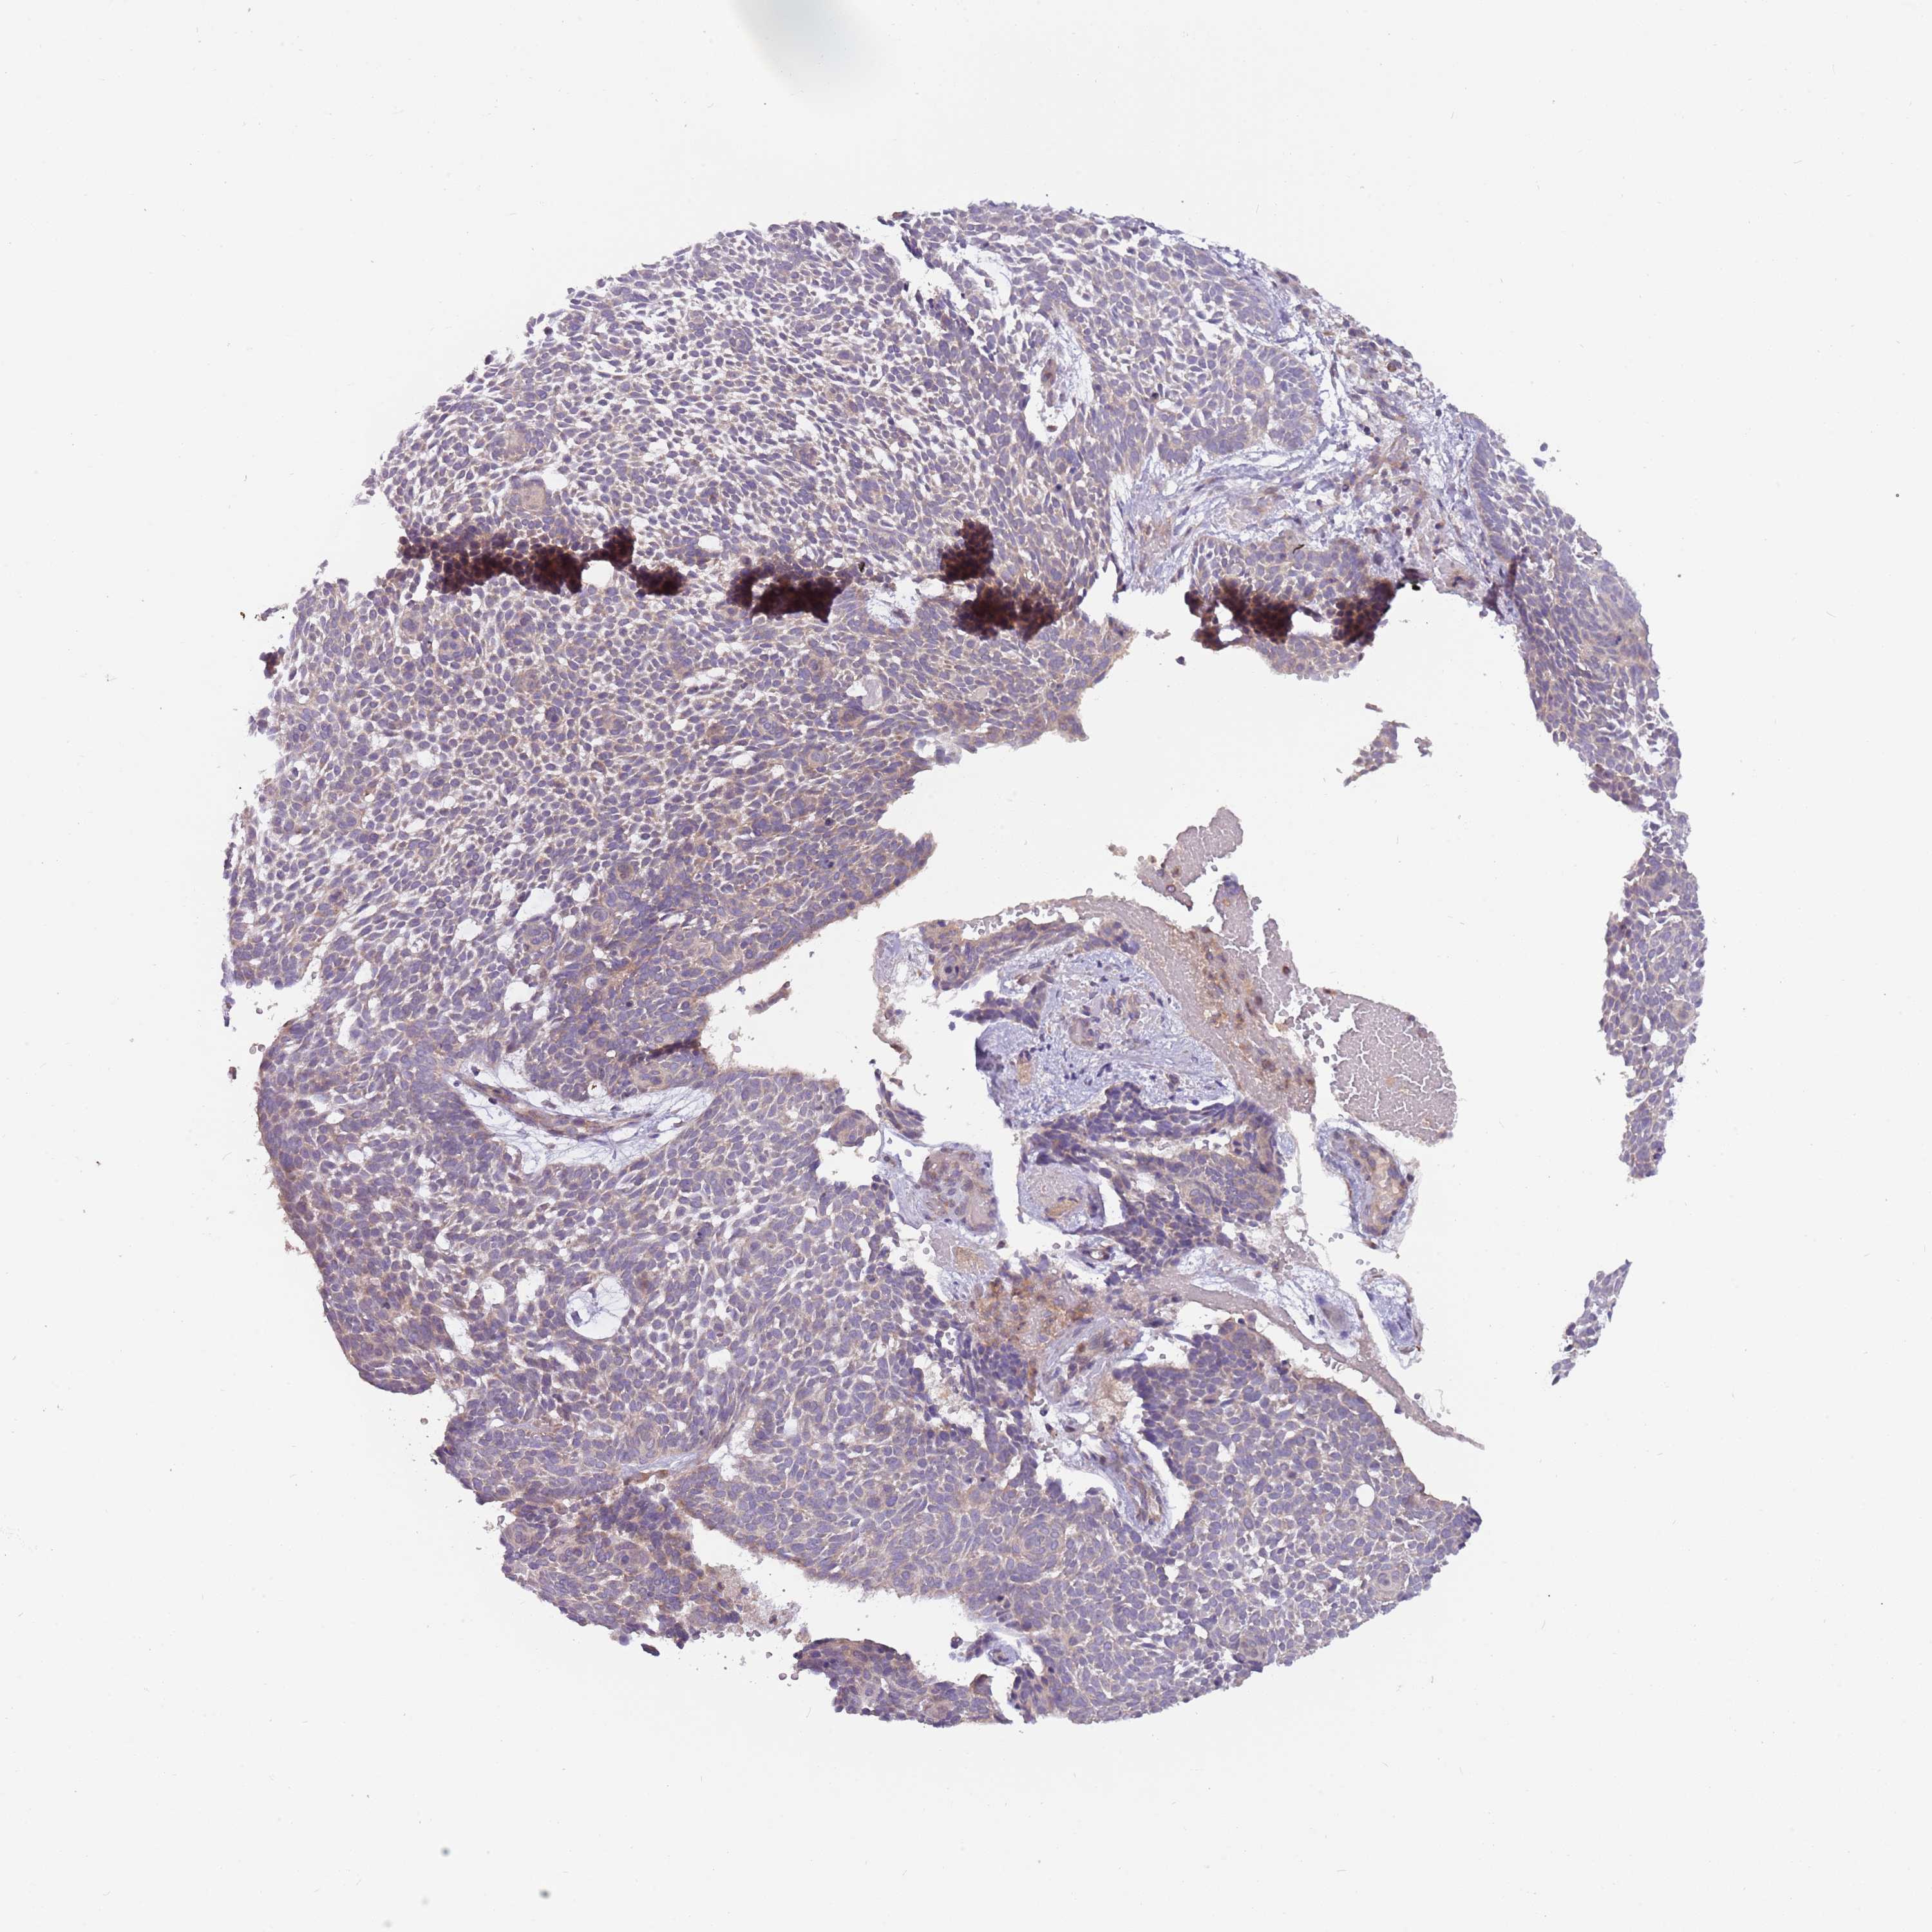

SKIN CANCER - Protein expressioni

A mouse-over function shows sample information and annotation data. Click on an image to view it in a full screen mode. Samples can be filtered based on level of antibody staining by selecting one or several of the following categories: high, medium, low and not detected. The assay and annotation is described here.

Antibody stainingi

Antibody staining in the annotated cell types in the current human tissue is reported as not detected, low, medium, or high, based on conventional immunohistochemistry profiling in selected tissues. This score is based on the combination of the staining intensity and fraction of stained cells.

Each image is clickable and will lead to virtual microscopy that enables deeper exploration of all samples and also displays staining intensity scores, fraction scores and subcellular localization as well as patient and tissue information for each sample.

Antibody HPA001117

Staining

High

Medium

Low

Not detected

Intensity

Strong

Moderate

Weak

Negative

Quantity

>75%

75%-25%

<25%

None

Location

Nuclear

Cytoplasmic/membranous

Cytoplasmic/membranous,nuclear

Basal cell carcinoma